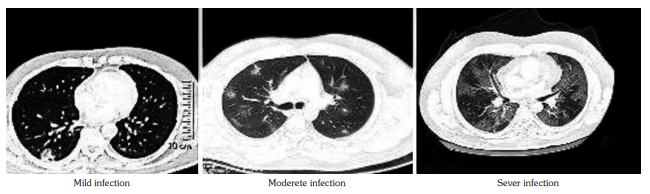

The patients with low (<30 ng/mL) baseline vitamin D level (vitamin D insufficiency and deficiency) significantly presented with more severe COVID-19 symptoms (68%) than patients with normal vitamin D levels (30.8%) (p<0.05). Also, the patients who presented with severe COVID-19 infection had low baseline vitamin D levels than those having mild-to-moderate symptoms (19.5±9.1 vs. 20.0±6.2 ng/mL, respectively; p<0.05). There was no significant difference in baseline vitamin D levels between the patients that were adherent to vitamin D supplementation and non-adherent group (p=0.1) (Figure 1, Tables 4 and 5).